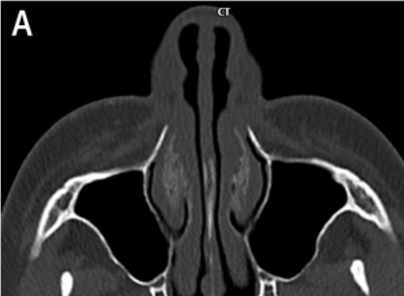

At VG Plastic Surgery, we carry out precise analysis and diagnosis procedures using 3D CT scans prior to surgery This is to analyze the problems that cannot be detected through consultation from a multi-faceted approach

An experienced plastic surgeon can determine the state of the nasal bone and the septal nasal cartilage based on a visual inspection alone. However, in order to determine the state of the nasal septum in the deeper parts, the degree of curvature of the nasal bone, the overall size and shape, and asymmetry, there is a need to perform a 3D analysis using 3D CT scans, which helps the surgeon formulate a more accurate and safer surgical plan. Of particular note, in the event of corrective nose surgery, a 3D analysis will reveal the state and notable characteristics of the implant and the septal nasal cartilage as well as the potential functional problems such as septal deviation in advance.

3D CT scans tailored to rhinoplasty procedures enable a multi-faceted analysis of the size and shape of the nasal bone, the septal nasal cartilage and the degree of curvature of the bone and/or cartilage and allow the surgeon to check for enlargement of the inferior nasal concha, presence of implants and determine the implant type and problems.